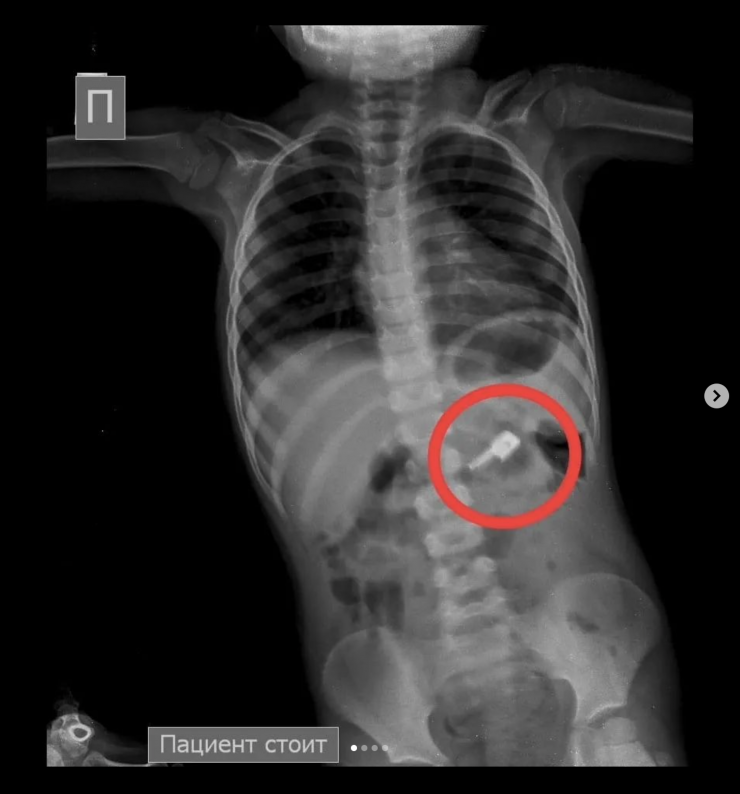

"На обзорной рентгенограмме брюшной полости был обнаружен бегунок и, предположительно, две швейные иглы в проекции желудка. При проведении процедуры ЭФГДС из желудка удалена одна игла, бегунок отсутствовал. Пациент был оставлен в хирургическом отделении Жамбылской областной многопрофильной детской больницы под наблюдением специалистов", - рассказали врачи детской больницы.